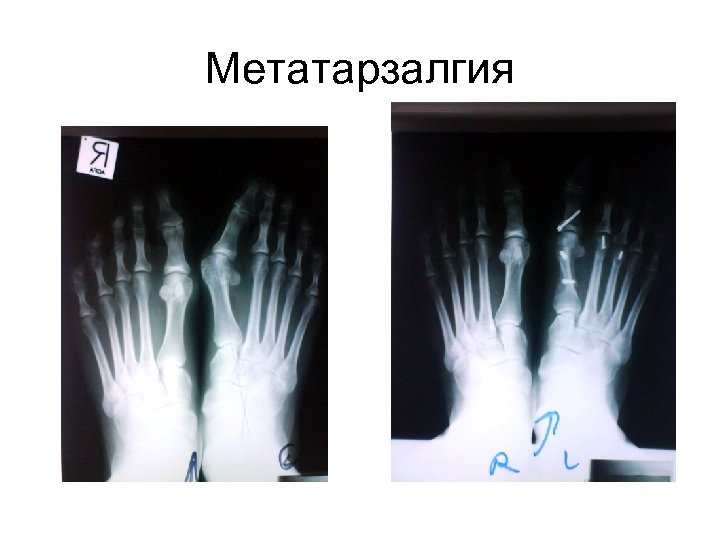

Другие операции • Деформация малых пальцев стопы • Метатарзалгия • Патология связок и сухожилии Другие операции • Деформация малых пальцев стопы • Метатарзалгия • Патология связок и сухожилии голеностопа • Опухоли стопы • Патология пятки и Ахиллесова Сухожилия • Шпора ( минимально инвазивная хирургия)

Метатарзалгия Метатарзалгия